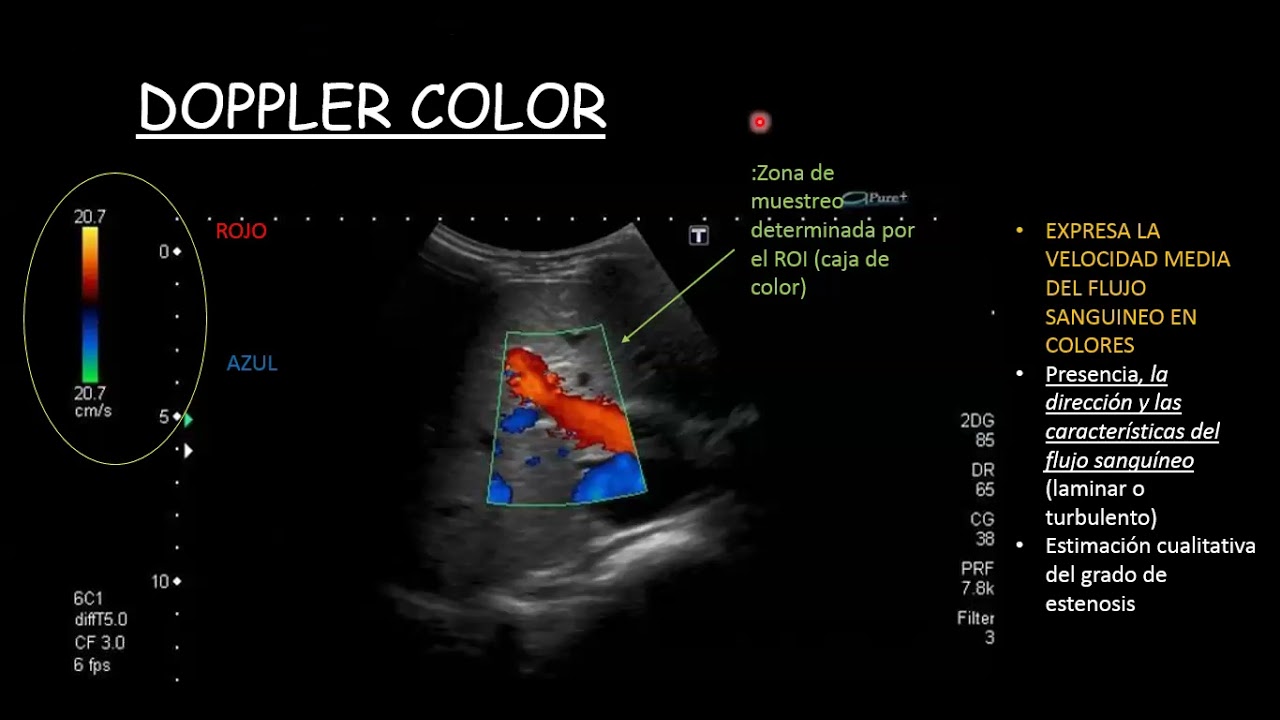

4. ¿que es el doppler color?

¿Quieres entender cómo funciona la tecnología detrás de las imágenes de Doppler color? ¡Este video es para ti! En este video explicaremos de manera clara y sencilla la física del Doppler color, desde los conceptos básicos hasta la aplicación en la medicina. Aprenderás cómo el Doppler color utiliza ondas de ultrasonido para medir la velocidad y dirección del flujo sanguíneo en el cuerpo humano, y cómo la tecnología de procesamiento de señales convierte estas mediciones en información visual. Además, conocerás las propiedades físicas del Doppler color, como la frecuencia de repetición de pulso, la ganancia y la sensibilidad, y cómo afectan a la calidad de las imágenes de Doppler color. Este video está diseñado para estudiantes de medicina que desean comprender los fundamentos de la tecnología de Doppler color. Verás ejemplos prácticos y explicaciones visuales que te ayudarán a comprender la física detrás de las imágenes de Doppler color. No pierdas la oportunidad de aprender cómo funciona la tecnología de Doppler color, una herramienta crucial en la práctica médica moderna. ¡Mira este video educativo ahora!